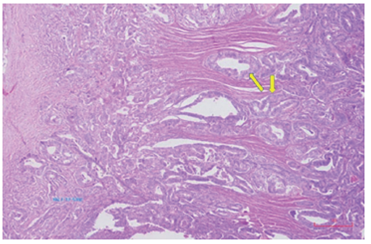

Según el estudio de histopatología de la pieza quirúrgica, se trataba de un adenocarcinoma de yeyuno, moderadamente diferenciado y polipoide, que invadía hasta la subserosa, y además, había invasión linfática y perineural. Los márgenes quirúrgicos y los ganglios linfáticos fueron negativos para tumor. Se clasificó como T3N0M0 (figuras 5, 6, 7).

Flechas: proliferación neoplásica glandular que afecta mucosa y submucosa, y atraviesa la pared muscular propia hasta la subserosa.

Fuente: Servicio de Patología, Hospital Irma Lourdes Tzanetato.

Figura 5. Proliferación glandular desordenada con glándulas de tamaños variables; epitelio atípico, caracterizado por pérdida de la polaridad, pleomorfismo nuclear, nucleomegalia y mitosis abundante. Hematoxilina eosina, 100X.